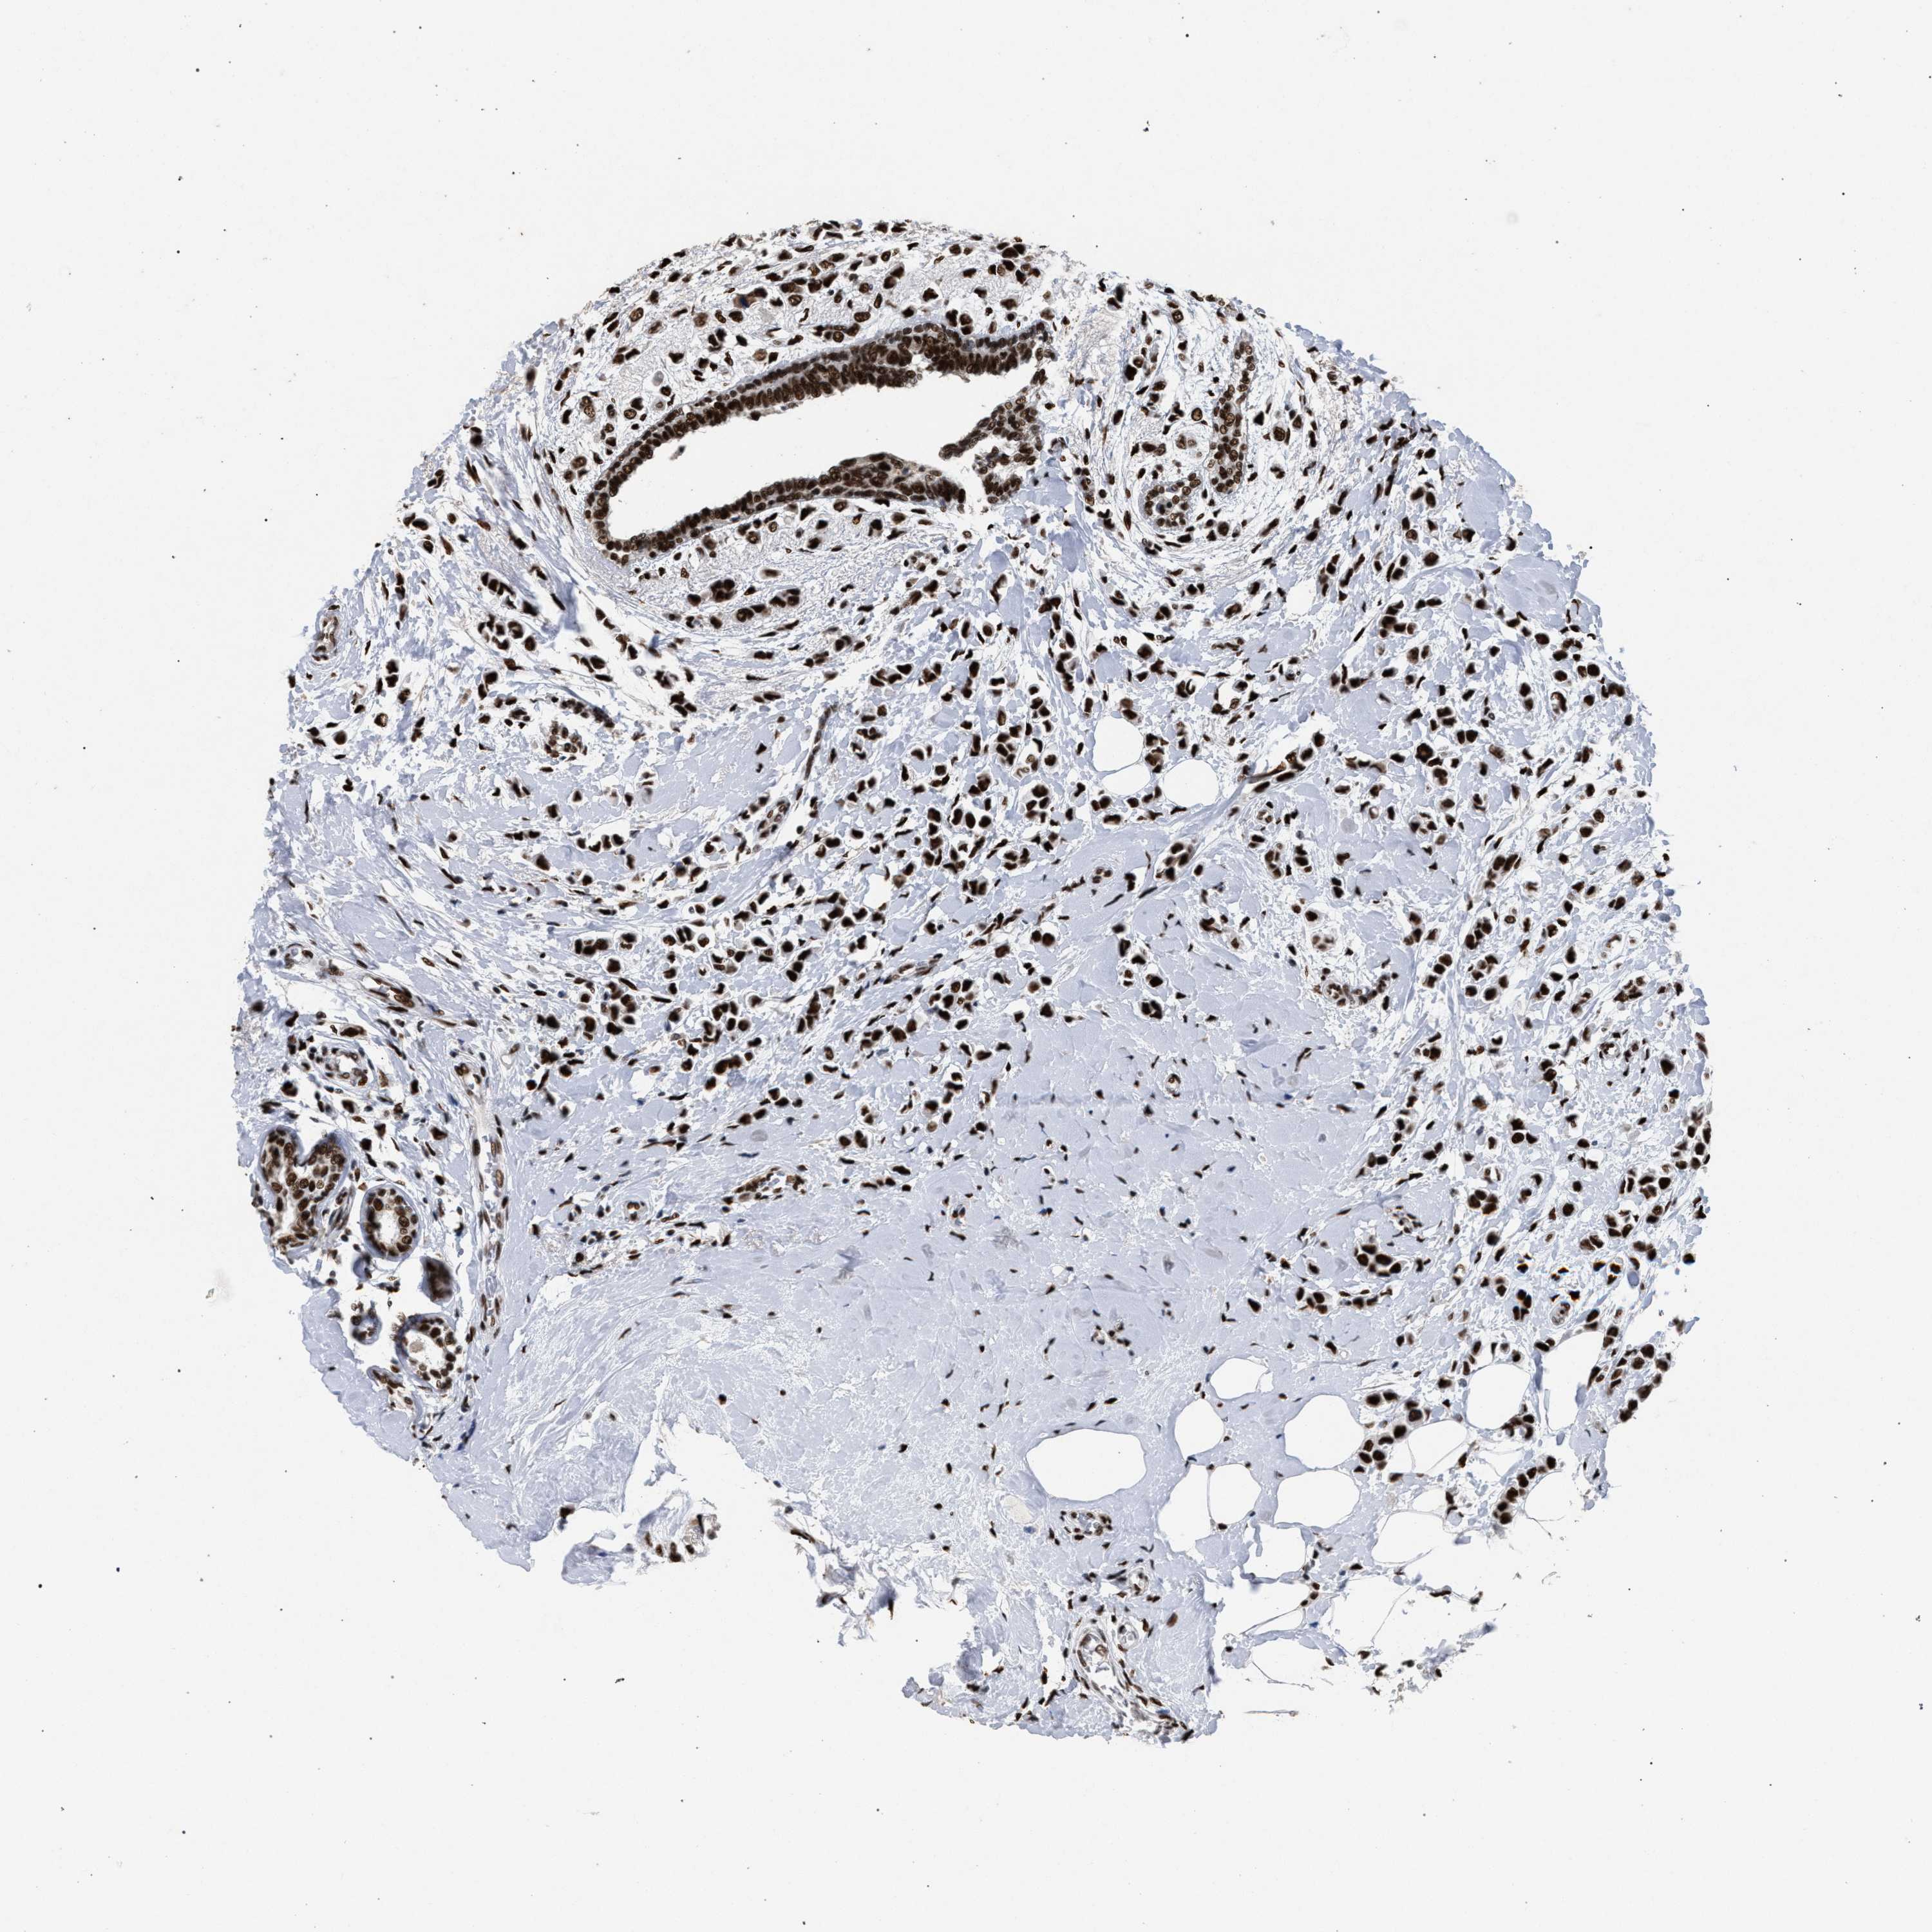

BRCA TCGA BRCA VALIDATION PROTEIN EXPRESSION

ANTIBODIES

AND

VALIDATION